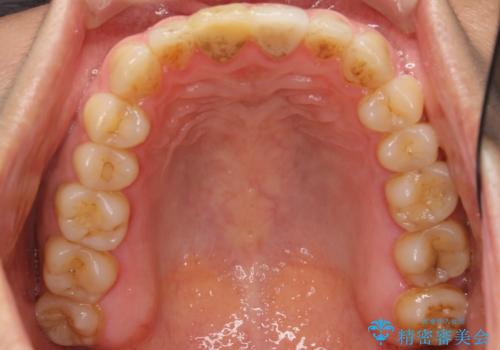

- 右上の前歯が折れたことを主訴に来院された患者様です。

歯が折れた部分は他院により応急処置で仮止めされていました。

欠けた範囲が大きかったため、セラミッククラウンによる補綴治療を行いました。

※左上の前歯(外国で治療されたとのこと)の失活が疑われたためそちらの治療も提案しましたが、ご希望されませんでした。